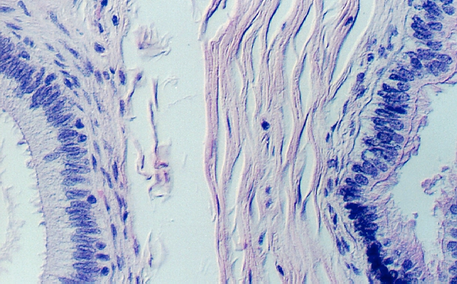

Seminiferous tubules contain the SPERMATAZOA in various stages of development along with the SERTOLI CELLS. Each tubule profile may show particular developmental stages in a high concentration, because development tends to occur in waves down the tubules. After the sperm are produced they travel to the TUBULI RECTI (straight tubules) which are found in the septa radiating from the mediastinum (see below). The tubuli recti connect the seminiferous tubules with the rete channels and tubules. The following photograph shows seminiferous tubules surrounding a connective tissue septum containing a tubulus rectus.